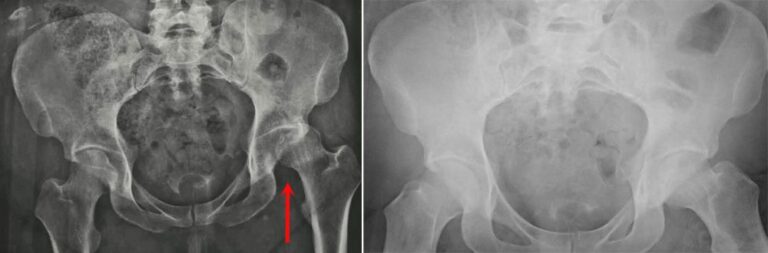

(Left) This X-ray, taken from the front, shows a patient with a posterior dislocation of the left hip. (Right) Normal alignment after the hip has been reduced.